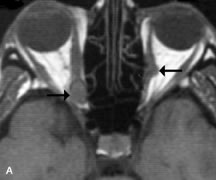

Lymphomas have MRI characteristics similar to those of inflammatory lesions in that they are hypointense to fat and isointense to muscle on T1-weighted images (Fig. 22). They may appear hyperintense to fat on T2-weighted images, perhaps owing to less fibrosis than that seen in orbital inflammatory pseudotumor, although this is not a consistent finding.31,50,66 Lymphoid tumors typically enhance moderately after contrast injection. Unfortunately, studies have shown that tumor density and homogeneity are similar between inflammatory and malignant orbital infiltrates, and MRI cannot differentiate these lesions.72,73

Fig. 22. A and B. T1- and (C) T2-weighted MR scans demonstrate a poorly defined multicompartmental mass enveloping the lateral rectus, superior rectus, and levator palpebrac superioris muscles. The lesion is isointense to brain on T1- and T2-weighted scans, as is typical for highly cellular neoplasms. D. Postcontrast fat-suppressed T1-weighted scan demonstrates intense enhancement of the infiltrating intraconal and extraconal tumor.